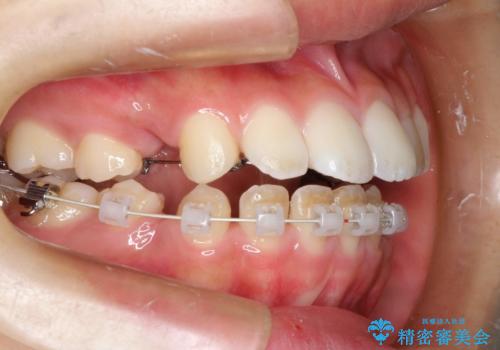

ハーフリンガル 半分裏側矯正による上下前突の抜歯矯正治療

- 20代女性

- 矯正装置

- ハーフリンガル

- 上下左右4本の第1小臼歯を抜歯する、抜歯矯正を計画した。

抜歯矯正により前歯の位置が後ろに下がり、わずかではありますが、口元に改善がみられ、歯並びもきれいに整いました。